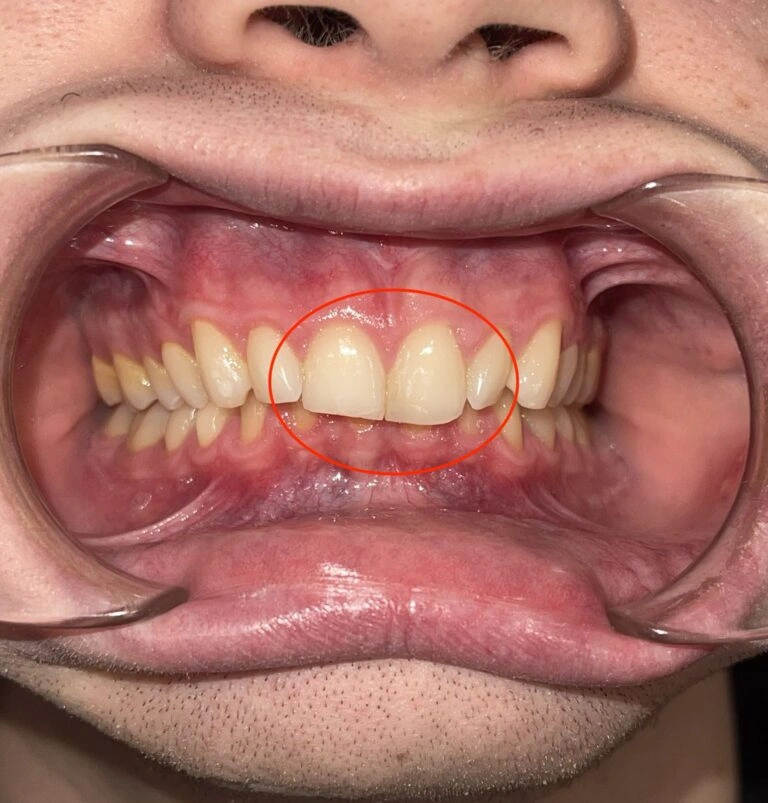

1. The Deep Bite: When Your Child’s Teeth Don’t Line Up Right

One of the most common problems I see is a deep bite.

This is a vertical issue where the upper teeth overlap the lower teeth so much that you can’t even see the bottom teeth.

Why should you worry? If a deep bite goes unaddressed, the teeth don’t meet properly. This misalignment can cause severe wear and tear on the teeth over time, eventually leading to tooth breakage and even tooth loss. I’ve treated many adults who came in with worn-down teeth due to untreated deep bites.

Here’s a visual example of what this looks like:

Patient Example #1: Notice how the teeth are significantly worn down and chipped due to long-term misalignment.